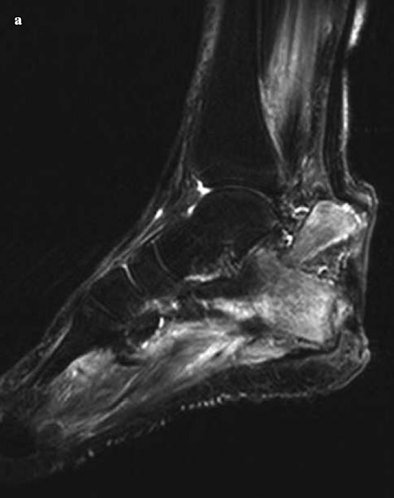

| The images show osteomyelitis of the calcaneus due to infected neuropathic ulcer of the heel. In (a), the sagittal short-tau inversion-recovery sequence image shows a pathological fracture of the calcaneus and dislocation of the proximal fragment due to retraction of the Achilles tendon. In (b), MR angiography of the right lower limb is hindered by venous contamination in the distal third, whereas the left infrapopliteal arteries are clearly visible up to the plantar arch. In (c), selective arteriography of the right lower limb shows normal infrapopliteal arteries and early venous filling due to inflammatory hyperaemia. Images courtesy of La Radiologia Medica and Carlo Poma Hospital, Mantua, Italy. |